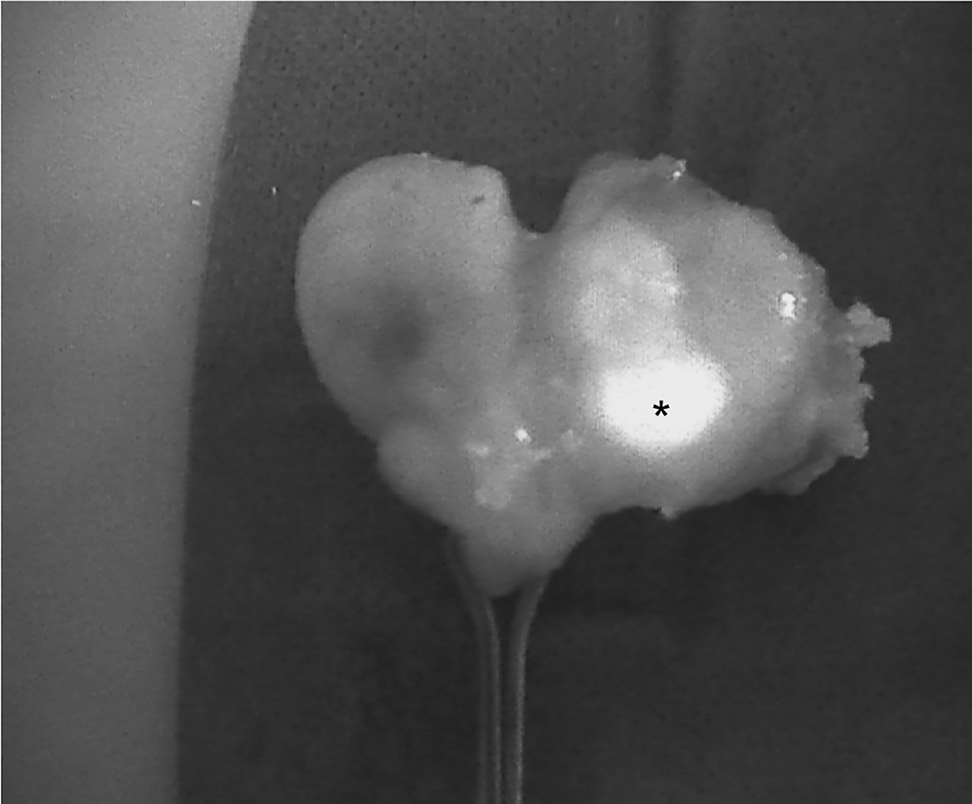

The introduction of NIRAF has vastly improved intraoperative imaging [47, 48]. Many recent studies (Table 2) have demonstrated that the use of NIRAF during thyroid surgery can improve surgical outcomes by facilitating PG identification (Figures 1 –3), which reduces the incidence of postoperative hypoparathyroidism. In particular, Benmilloud et al. showed that NIRAF improved PG identification and helped to reduce the rate of temporary postoperative hypocalcemia, parathyroid autotransplantation, and inadvertent parathyroid resection [48, 66]. In the literature, NIR devices have been shown to facilitate parathyroid gland identification by detecting their AF before conventional, visual recognition by the surgeon, in 37–67% of cases [49]. Additionally, these devices enable the early identification of PGs before surgical dissection, helping to preserve their vasculature [50]. A systematic review and meta-analysis by Barbieri et al. found that NIR fluorescence imaging reduced short and medium-term hypocalcemia compared to conventional surgery [51]. Moreover, NIRAF can detect subcapsular/intrathyroidal PGs or PGs that have been accidentally removed, which can then be resected from the thyroid specimen and auto planted back into the patient (Figures 4 and 5). In addition to the identification of normal PGs, NIRAF can help to identify a pathological PG. Parathyroid adenomas exhibit a more heterogeneous and less intense autofluorescence signature than that of normal PGs (Figure 6), enabling the differentiation between a normally functioning and a pathological PG [52, 53]. Furthermore, the fluorophore is resistant to freezing, heating, and fixing with formalin, meaning that the autofluorescence properties are preserved after gland resection [4, 29, 42, 43].

Intraoperative near-infrared autofluorescence (NIRAF) images of parathyroid adenomas after resection, demonstrating the heterogeneous and less intense fluorescence pattern that differentiates diseased parathyroid glands (PGs) from normal PGs (indicated with *). Frequently, the most intense NIRAF signal comes from residual normal parathyroid tissue in the adenoma.